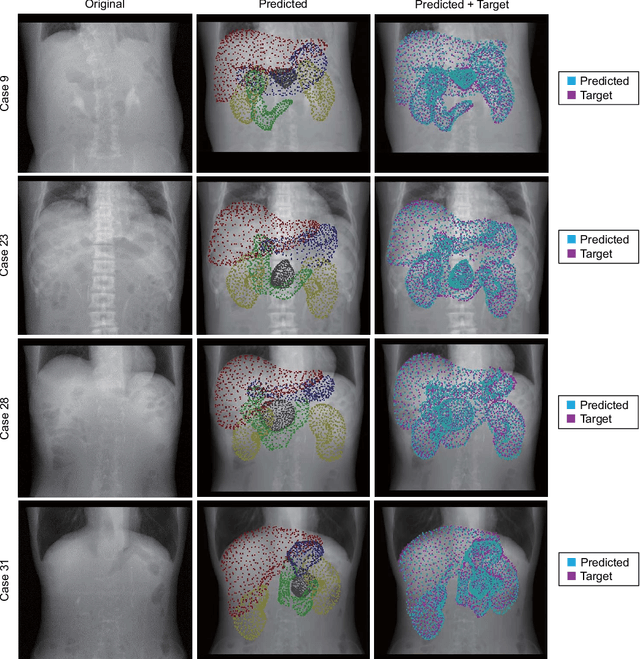

Abstract:Deformable registration of two-dimensional/three-dimensional (2D/3D) images of abdominal organs is a complicated task because the abdominal organs deform significantly and their contours are not detected in two-dimensional X-ray images. We propose a supervised deep learning framework that achieves 2D/3D deformable image registration between 3D volumes and single-viewpoint 2D projected images. The proposed method learns the translation from the target 2D projection images and the initial 3D volume to 3D displacement fields. In experiments, we registered 3D-computed tomography (CT) volumes to digitally reconstructed radiographs generated from abdominal 4D-CT volumes. For validation, we used 4D-CT volumes of 35 cases and confirmed that the 3D-CT volumes reflecting the nonlinear and local respiratory organ displacement were reconstructed. The proposed method demonstrate the compatible performance to the conventional methods with a dice similarity coefficient of 91.6 \% for the liver region and 85.9 \% for the stomach region, while estimating a significantly more accurate CT values.

Abstract:Organ shape reconstruction based on a single-projection image during treatment has wide clinical scope, e.g., in image-guided radiotherapy and surgical guidance. We propose an image-to-graph convolutional network that achieves deformable registration of a 3D organ mesh for a single-viewpoint 2D projection image. This framework enables simultaneous training of two types of transformation: from the 2D projection image to a displacement map, and from the sampled per-vertex feature to a 3D displacement that satisfies the geometrical constraint of the mesh structure. Assuming application to radiation therapy, the 2D/3D deformable registration performance is verified for multiple abdominal organs that have not been targeted to date, i.e., the liver, stomach, duodenum, and kidney, and for pancreatic cancer. The experimental results show shape prediction considering relationships among multiple organs can be used to predict respiratory motion and deformation from digitally reconstructed radiographs with clinically acceptable accuracy.